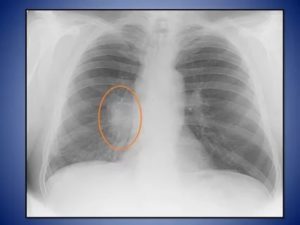

Описание снимка при онкологии

Опухоль на рентгене выглядит, как «плюс-ткань» или характерное затемнение. Её контуры, как правило, нечёткие, так как онкологическое заболевание прогрессирует, распространяясь на здоровые клетки. Чем темнее изображение, тем сильнее поражение тканей. Наличие округлых очертаний говорит о наличии в органе метастазов.

На второй стадии рака поражаются локальные лимфоузлы, это выражается в нарушении структурности корня лёгких. Лимфатические ткани увеличиваются в размерах, формируются метастазы.

На более поздних стадиях опухоль уже достаточно большая, распространяется на значительную часть органа. Усиливается лёгочный рисунок, поскольку растущее новообразование требует усиленного кровоснабжения, в связи с чем наблюдаются признаки гипертензии. Часто наблюдается плеврит – визуализируется контур плевры, просматривается патологический транссудат – жидкость в синусах органа.

Особенности, погрешности

На рентгеновском снимке воспалительный и опухолевый процессы выглядят почти одинаково. При интерпретации изображения учитывают такие особенности типичной рентгенограммы опухоли:

- лёгочный рисунок – не меняется;

- в прилежащих отделах тени отсутствуют или являются одиночными;

- поражённые ткани имеют бугристую поверхность, лучистые контуры;

- корни лёгких изменены только на последних стадиях;

- тени имеют однородный оттенок.